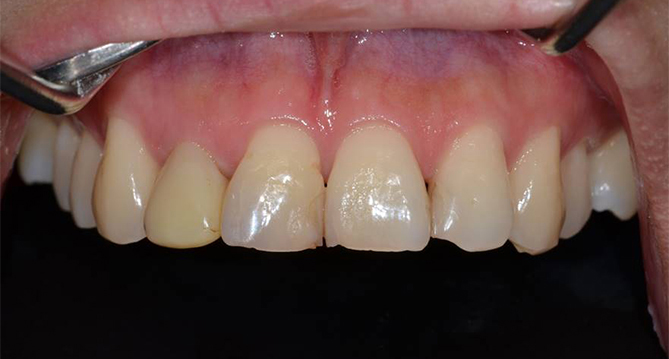

치아의 기능과 심미성 회복을 위한 치료로

정확한 치료계획이 필요한 보철치료

보철과 전문의의 자연치아보호하기, 금이 갔거나 심한 충치로 인해

상실 또는 손상된 치아를 견고하고 심미적인 보철물을 통해 기능과 심미성 회복을 도와줍니다.

연세새빛치과는 보철과 전문의가 정확하게 개인별 맞춤치료계획을 수립하여

남아있는 자연치들이 상실된 기능을 회복하고 주변치아의 치아질환예방과 전체적인 심미성까지 고려합니다.

심미성이 중요한 전치부 보철물은 더욱 더 전문성이 필요합니다.

연세새빛치과는 보건복지부인증 보철과 전문의의 정확한 진단과

정석적이고 체계적인 치료를 진행합니다.

브릿지치료

상실치아의 양 옆의 치아모양을 다듬은 후 여러개의 크라운

보철물을 연결하여 치아의 심미성과 기능을 회복시키는

보철물의 한 종류입니다.